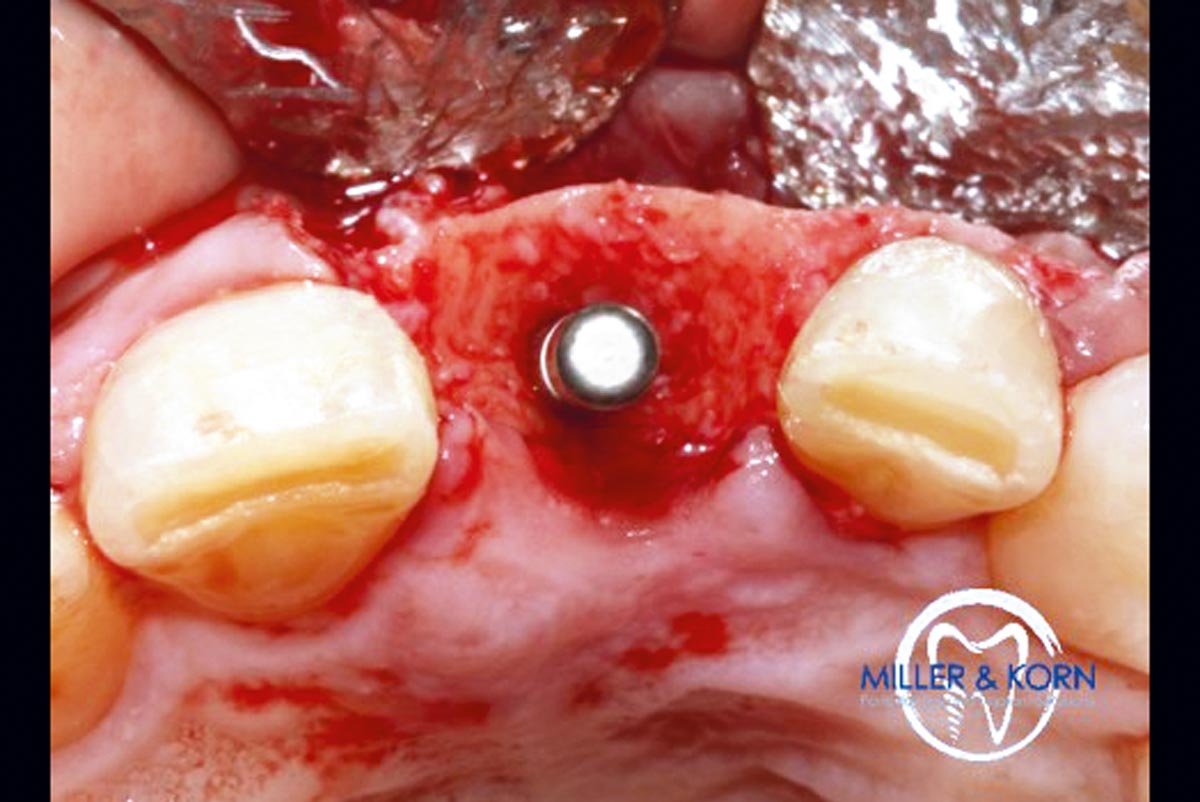

19/39 - Immediate implant insertion through the bone ringImmediate implant placement and correction of horizontal and vertical bone loss using an allograft bone ring, cerabone® and Jason® membrane - Drs. Miller and Korn